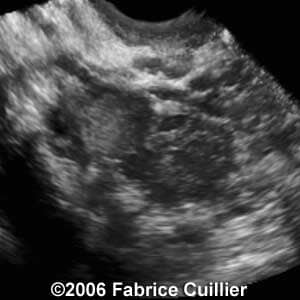

Case 3

case3a

case3b